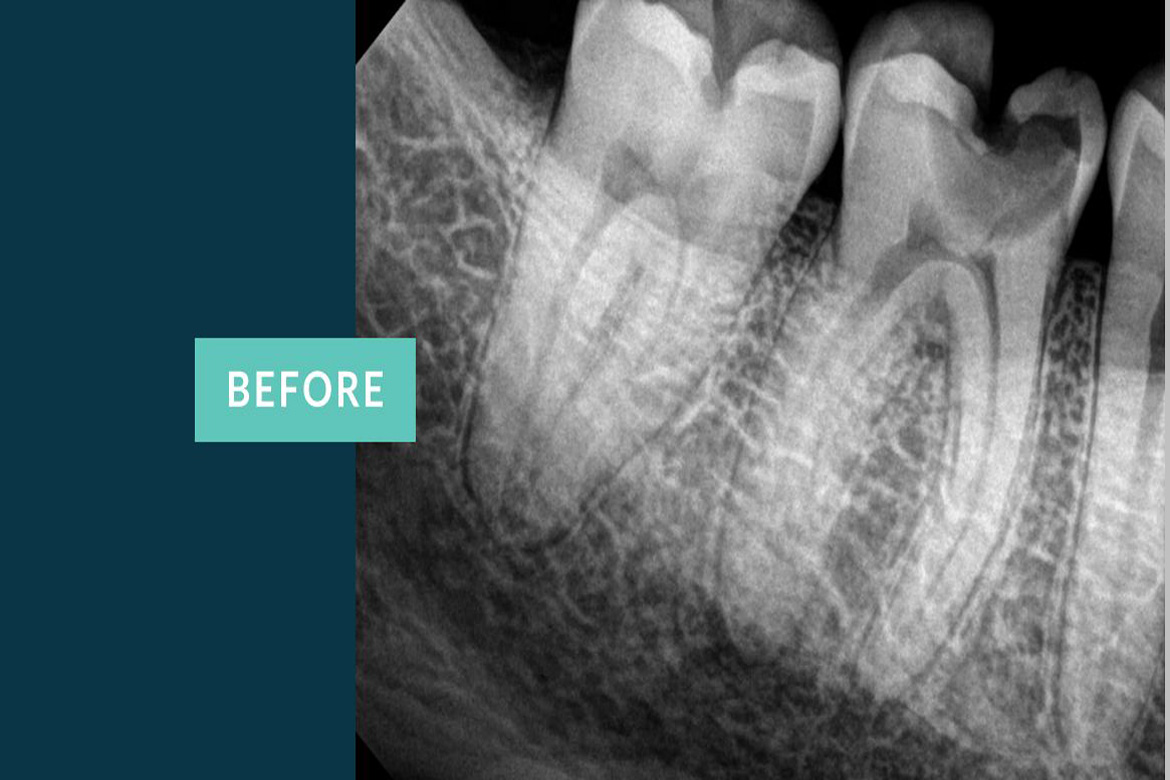

The primary intent of Root canal treatment is to remove the diseased pulp ,clean ,cleanse ,irrigate shape and then fill the canals of the tooth.

Root canal is filled completely with an inert material called Guttaperchathis is to advocate periradicular healing and prevent reinfection of the tooth there by preserving the natural tooth thus maintaining the balance in the oral cavity.

Thanks to the advanced technology which introduced Nickel-Titanium rotary instuments,apexlocators,ultrasonics,lasers and microscopic endodontics which maked the work of a Dentist easy and hasslefree . These latest inventions helped the dentists achieve dental procedures more precisely than before.